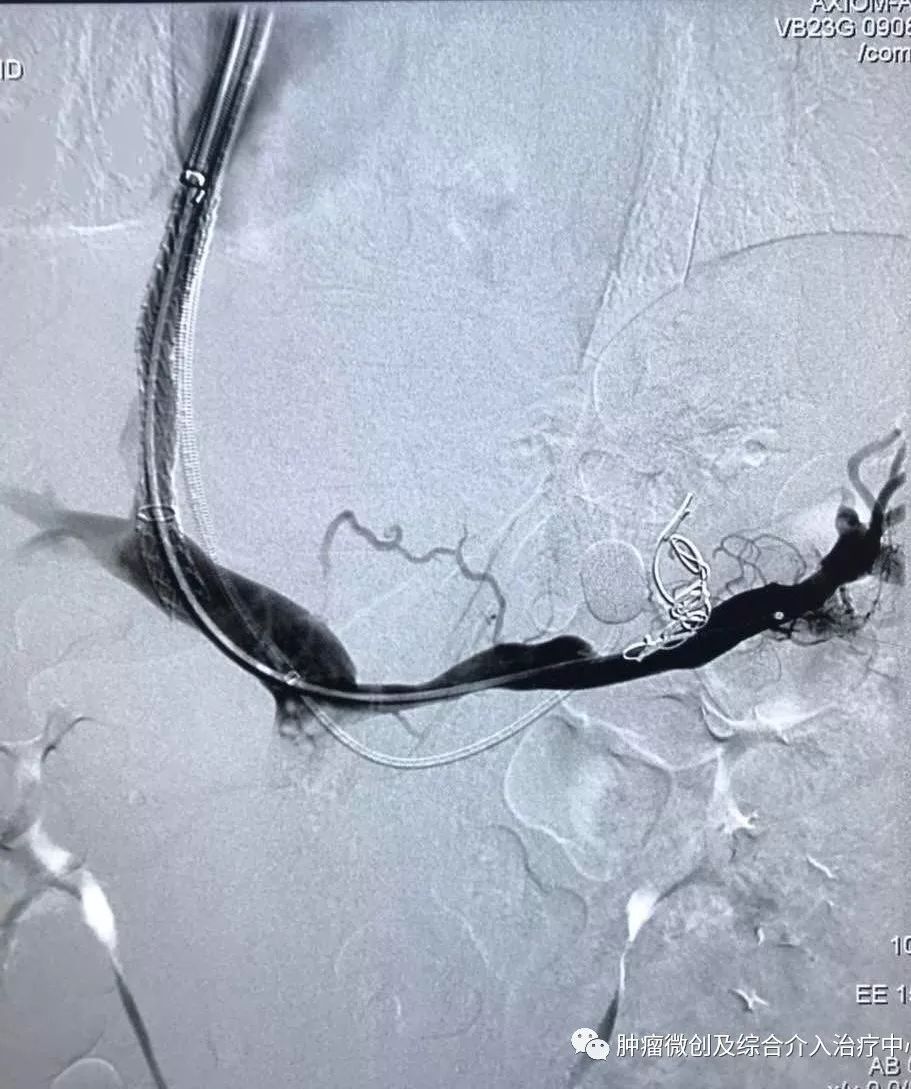

(术前DSA造影提示肠系下动脉增粗、增多、絮乱,临床表现为便血,系破裂出血)

(介入栓塞术后造影提示肠系膜下直肠动脉走向规则,清晰,术后出血症状停止,血压明显稳定)